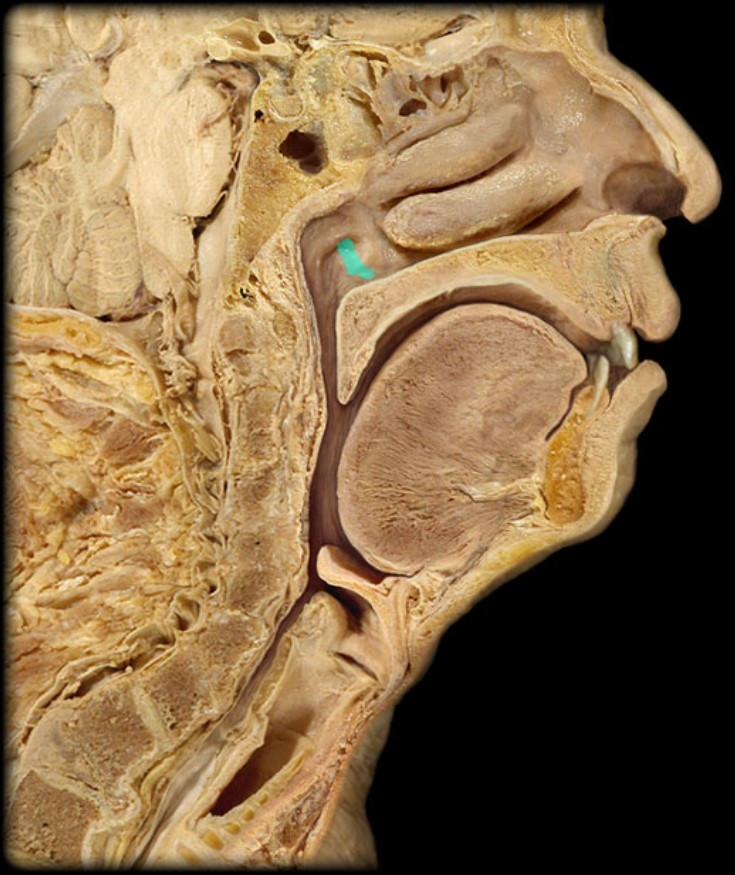

Sphenoid Sinus

24

New cards

Inferior Nasal Concha

25

New cards

Middle Nasal Concha